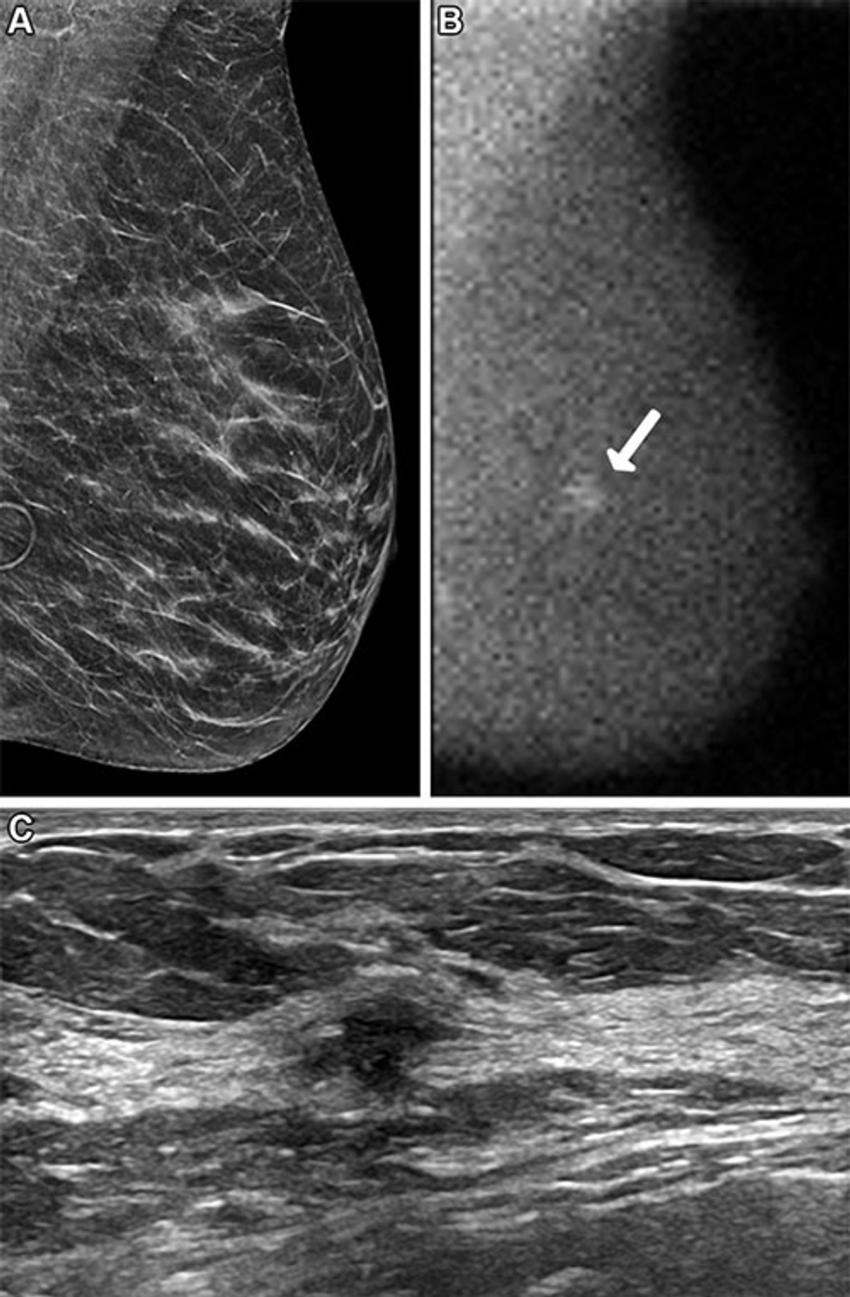

Figure 3. Images in a 57-year-old woman who presented for screening. (A) Image from digital breast tomosynthesis screening (synthesized two-dimensional mediolateral oblique view of the left breast) at year 1 was interpreted as negative and showing heterogeneously dense breast. (B) Image from molecular breast imaging screening (mediolateral oblique view) at year 1 reveals a 2-cm mass in the left breast (arrow). (C) Targeted US scan (transverse image) reveals a corresponding irregular hypoechoic mass in the 1-o’clock position, 5 cm from the nipple. US-guided core biopsy and lumpectomy revealed a 2.6-cm grade 2 invasive ductal carcinoma, an estrogen receptor–positive, progesterone receptor–negative, human epidermal growth factor receptor 2–positive lesion, with two sentinel nodes negative (N0).